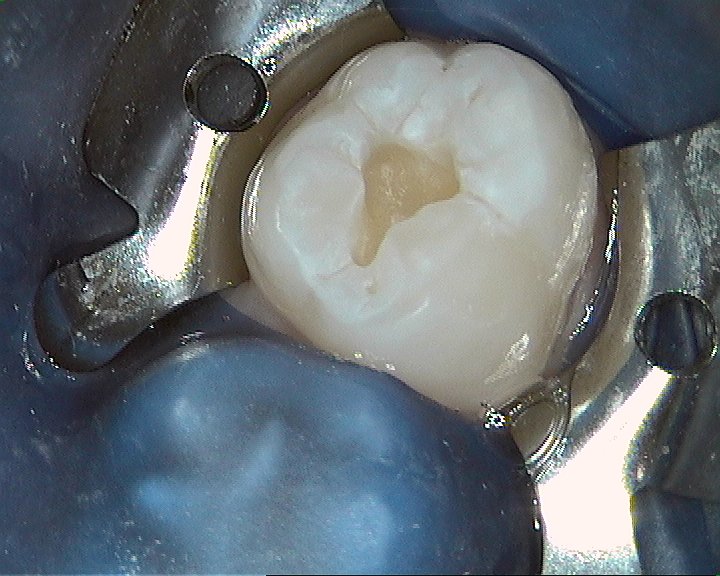

![]() Der "Regenschirm" oder Kofferdam- Spanngummi für kontrollierte Arbeitsbedingungen auch oder gerade in kleinen Mündern. So hält die Füllung bis zum natürlichen Zahnwechsel mit ca. 11 Jahren!